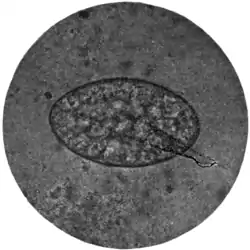

Fig. 194.—Ovum of Fasciolopsis buski, x 250. (Photograph by Dr. J. Bell.)

lies behind the posterior testis; there are a receptaculum seminis and a Laurer's canal. The yolk glands lie in the lateral portion of the middle fifth of the body. The eggs are thick-shelled, yellowish-brown in colour, and measure 38-45 μ by 22-30 μ. Nothing is known of the life-history of the parasite.